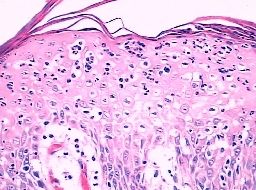

北京京城皮肤医院指出,艾滋病的皮肤损害-面部感染较明显。

艾滋病感染性皮肤损害-细菌感染:表现为毛囊炎、多发性皮肤脓肿或疖。

艾滋病感染性皮肤损害-痤疮:皮损分布广泛,从面、胸、背延及臀部,甚至小腿,有黑头粉刺和囊肿形成。